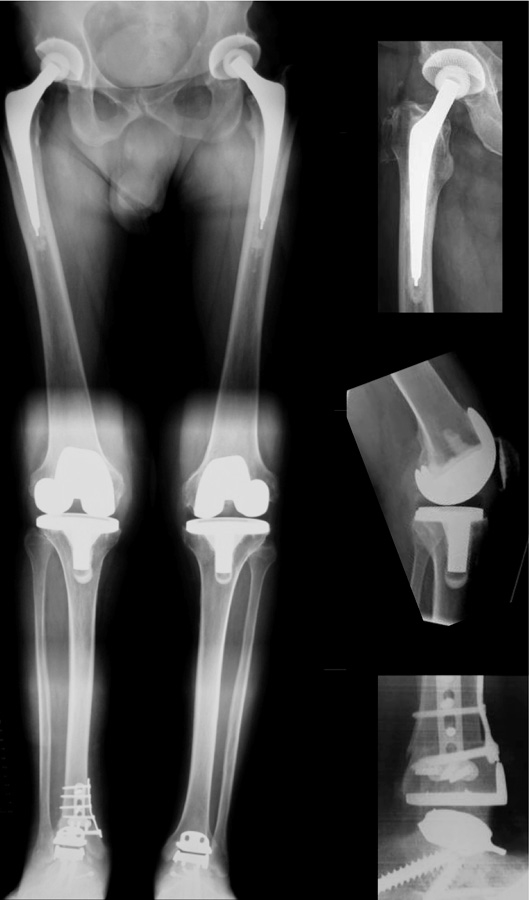

Figure 7

Multi-level surgery: 53 year old patients with rheumatoid and psoriasis arthritis, consistent of two total hip arthroplasties, two total knee arthroplasties, realignment surgery of the right ankle, and two total ankle replacements.

Severe OA accompanied with profound deformities are very often not limited to one joint only. To restore normal biomechanics the therapy of choice is to address every level of the kinematic chain. Otherwise the destruction of the adjacent joints proceeds, resulting in further aberrant mechanical alignments and advanced wear of the replaced joint. Multi-level surgery might provide a solution in these severe cases (fig. 7). Although extensive preoperative planning and precise patient selection are crucial, because these highly invasive procedures demand a great deal of the patient and require a close guidance and adequate patient compliance.